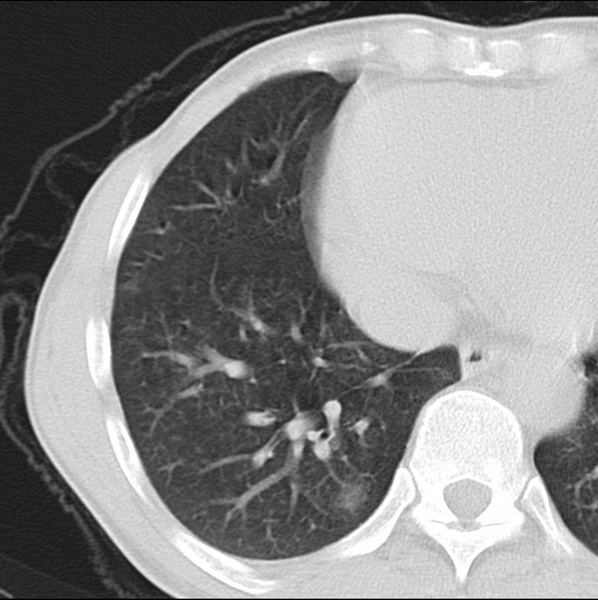

男、48、咳嗽。

胸片示双肺纹理紊乱,行胸部ct检查。

右肺下叶基底段结节影,双肺粟粒样阴影,ct值测量约-20hu左右,可能不准。

层厚层距为4mm左右,病灶轴面最大径约1cm左右。